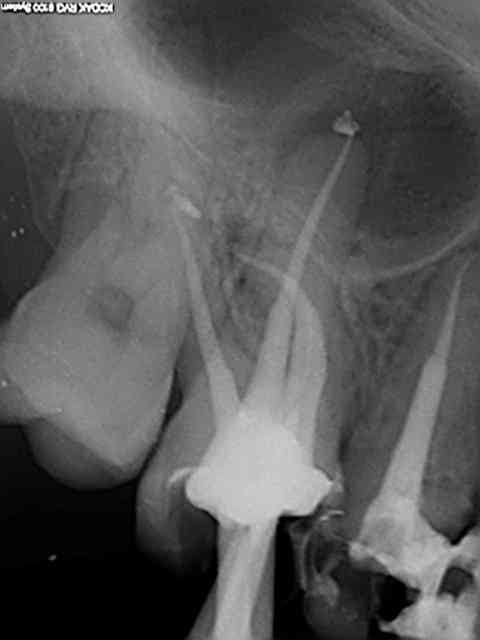

Marc tu cherches midi à 14 H. Séquence utilisée pour ces 16 et 26 (MV2 inclus) sans aide optique ni controle visuel de toutes facons tout à la "sensation". Aucun des instruments utilisés ne fait de faux canaux (largo sur double bague verte contre angle endo sur un bague bleue je ne répond plus de rien lol !)) Et je peux te dire que j'en ai essayé des systèmes ! Contrairement à ce que tu dis les s1 et S2 protaper cassent rarement ce sont les F1 ET F2 qui cassent pour un oui ou pour un non sauf évidemment si ils ne servent à rien (canal large ou déjà préparé )!))))))

SX, R25, Largo 3, SX, S1, R25, S1 (apex), R25 ( apex).